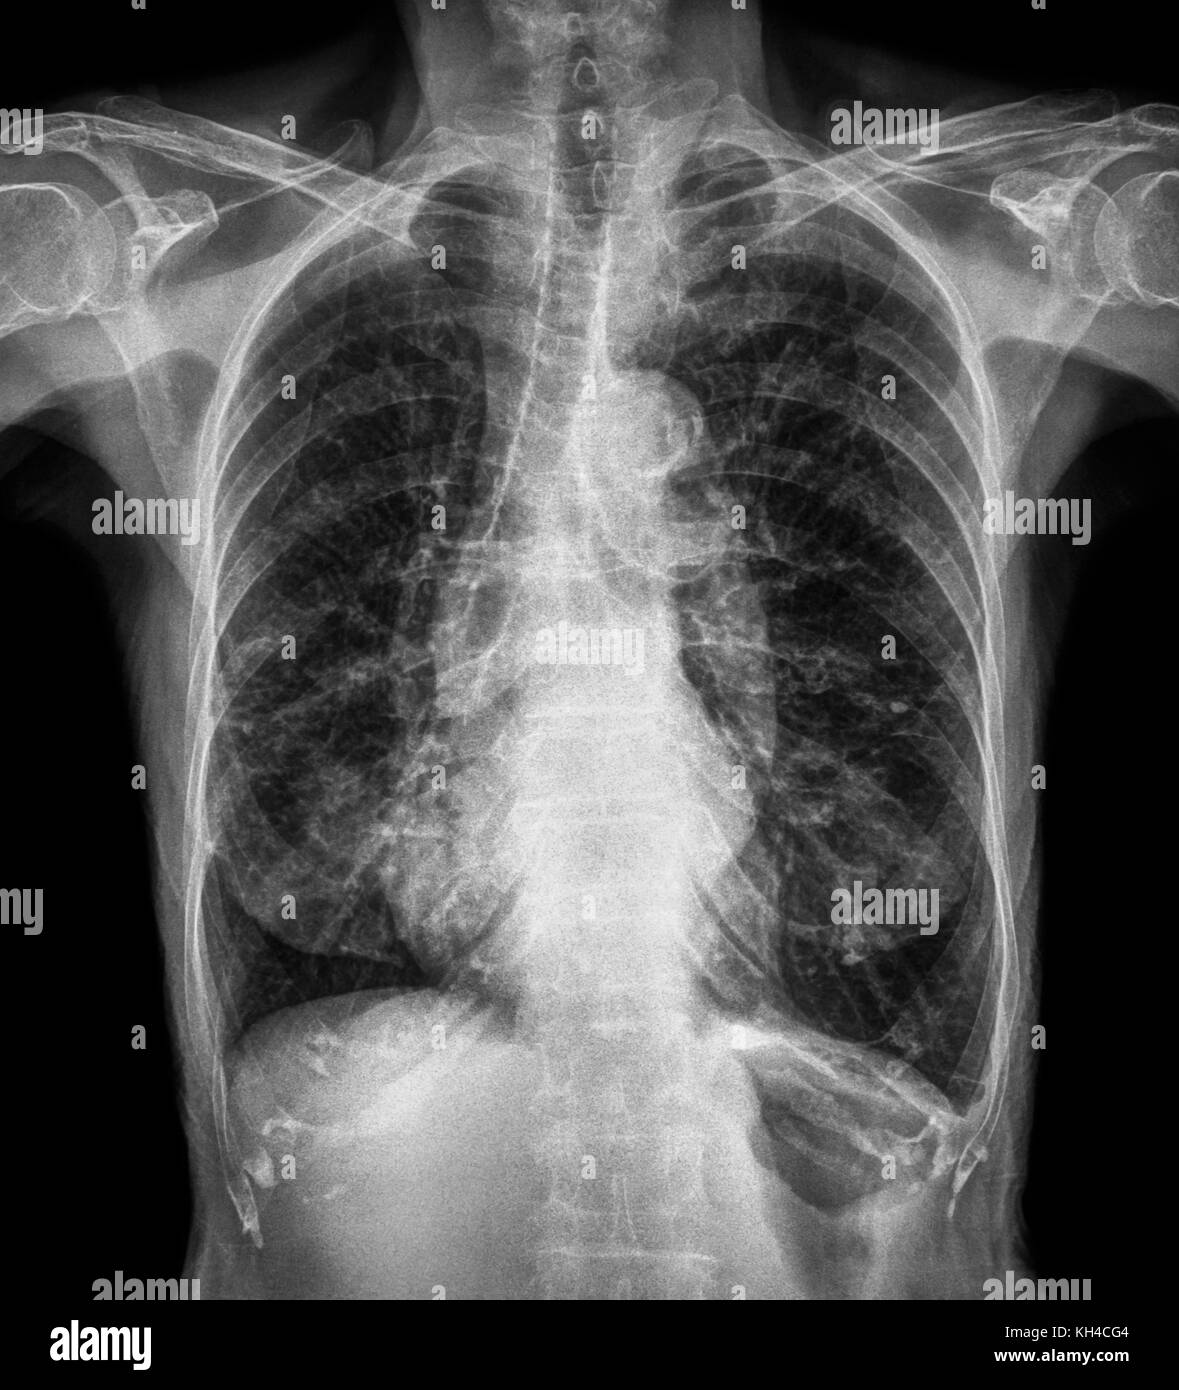

Normal chest Xray of old patient . You can seen calcification at rib

Normal chest Xray of old patient . You can seen calcification at rib Small Spots On Chest X Ray Lung nodules are commonly found after a patient undergoes a chest ct scan for some reason, such as when a patient experiences symptoms of lung disease or during a lung cancer screening. lung nodules (also called pulmonary nodules) are spots or shadows that may show up in the lung during a. a lung nodule is a small mass. Small Spots On Chest X Ray.